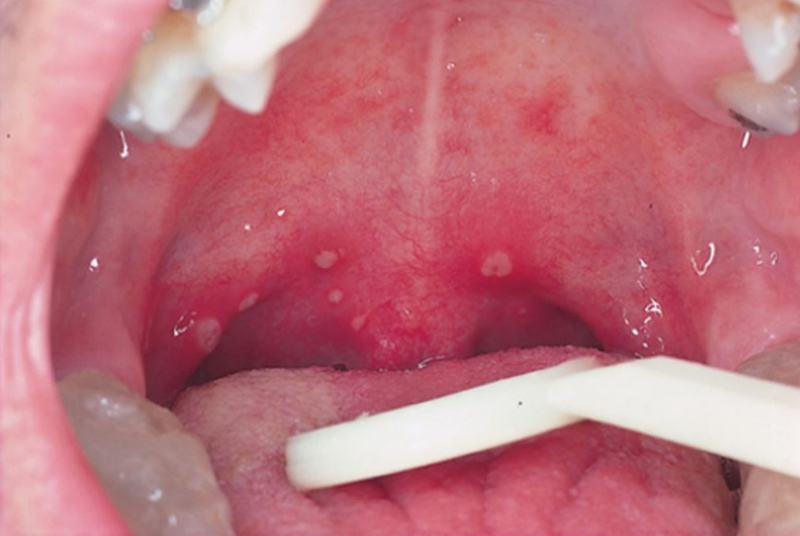

Bệnh Herpangina do virus gây ra là bệnh truyền nhiễm cấp tính, đặc trưng bởi triệu chứng sốt cao kèm theo nổi nốt mụn nước và vết loét niêm mạc miệng. Tuy bệnh thường diễn biến lành tính nhưng vẫn có một số trường hợp có thể tiến triển làm tổn thương thần kinh.

Để chẩn đoán bệnh Herpangina, bác sĩ thường chỉ dựa vào khai thác tiền sử tiếp xúc, diễn biến triệu chứng bệnh và thăm khám lâm sàng. Trong những trường hợp bệnh nhẹ, tổn thương vết loét miệng trên lâm sàng đặc trưng, bác sĩ thường chẩn đoán xác định bệnh.